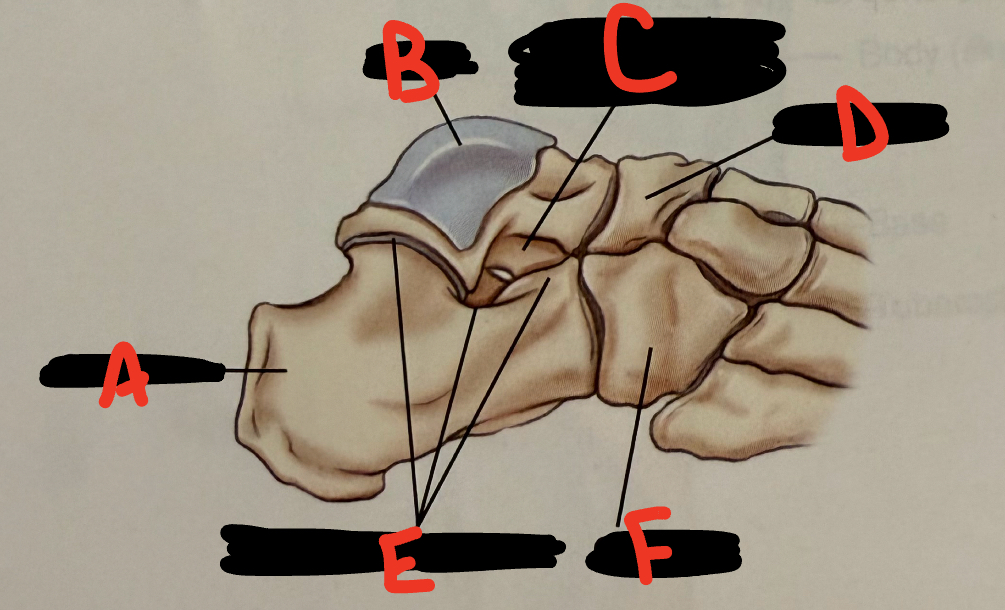

anterior tubercle

5

<p>E</p>

E

talus

6

New cards

<p>A</p>

A

fibula

7

<p>B</p>

B